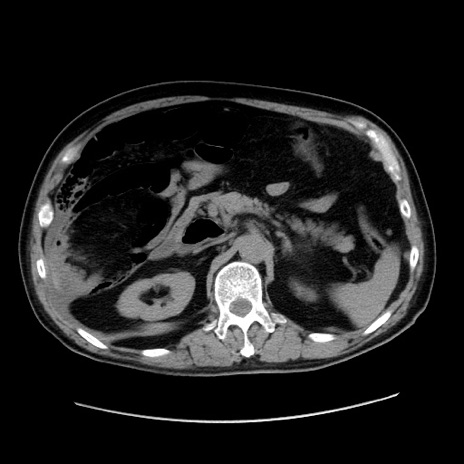

症例30(横断像)

【症例】80歳代男性

【主訴】臍周囲痛

【現病歴】約6時間前から臍下部痛が出現。次第に腹部膨隆・背部痛も生じてきたため来院。背部痛の場所は変化しない。

【既往歴】腎盂腎炎

【身体所見】意識清明、BT 36.3℃、BP  131/87mmHg、P 87bpm、SpO2 100%(RA)、臍周囲自発痛・圧痛あり、反跳痛なし、自発痛部位に一致して板状硬あり、腹部膨隆、腸雑音減弱、CVA tenderness両側陰性。

【データ】WBC 19600、CRP 0.33